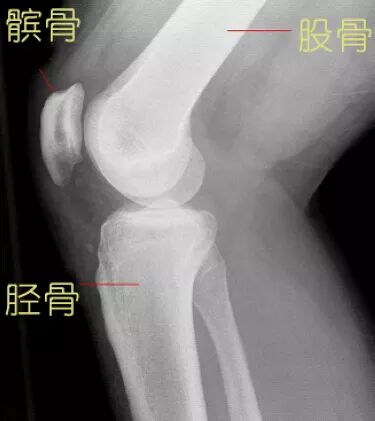

膝关节作为人体最大最复杂的关节,由股骨下端、胫骨上端和髌骨共同构成。其中胫骨上端基本上是一个平面,而股骨下端的关节面则是一个椭圆形,两个关节面一圆一平,并不完全贴和,所以需要半月板来帮助关节面完整贴和。

膝关节X光片(矢状面)。